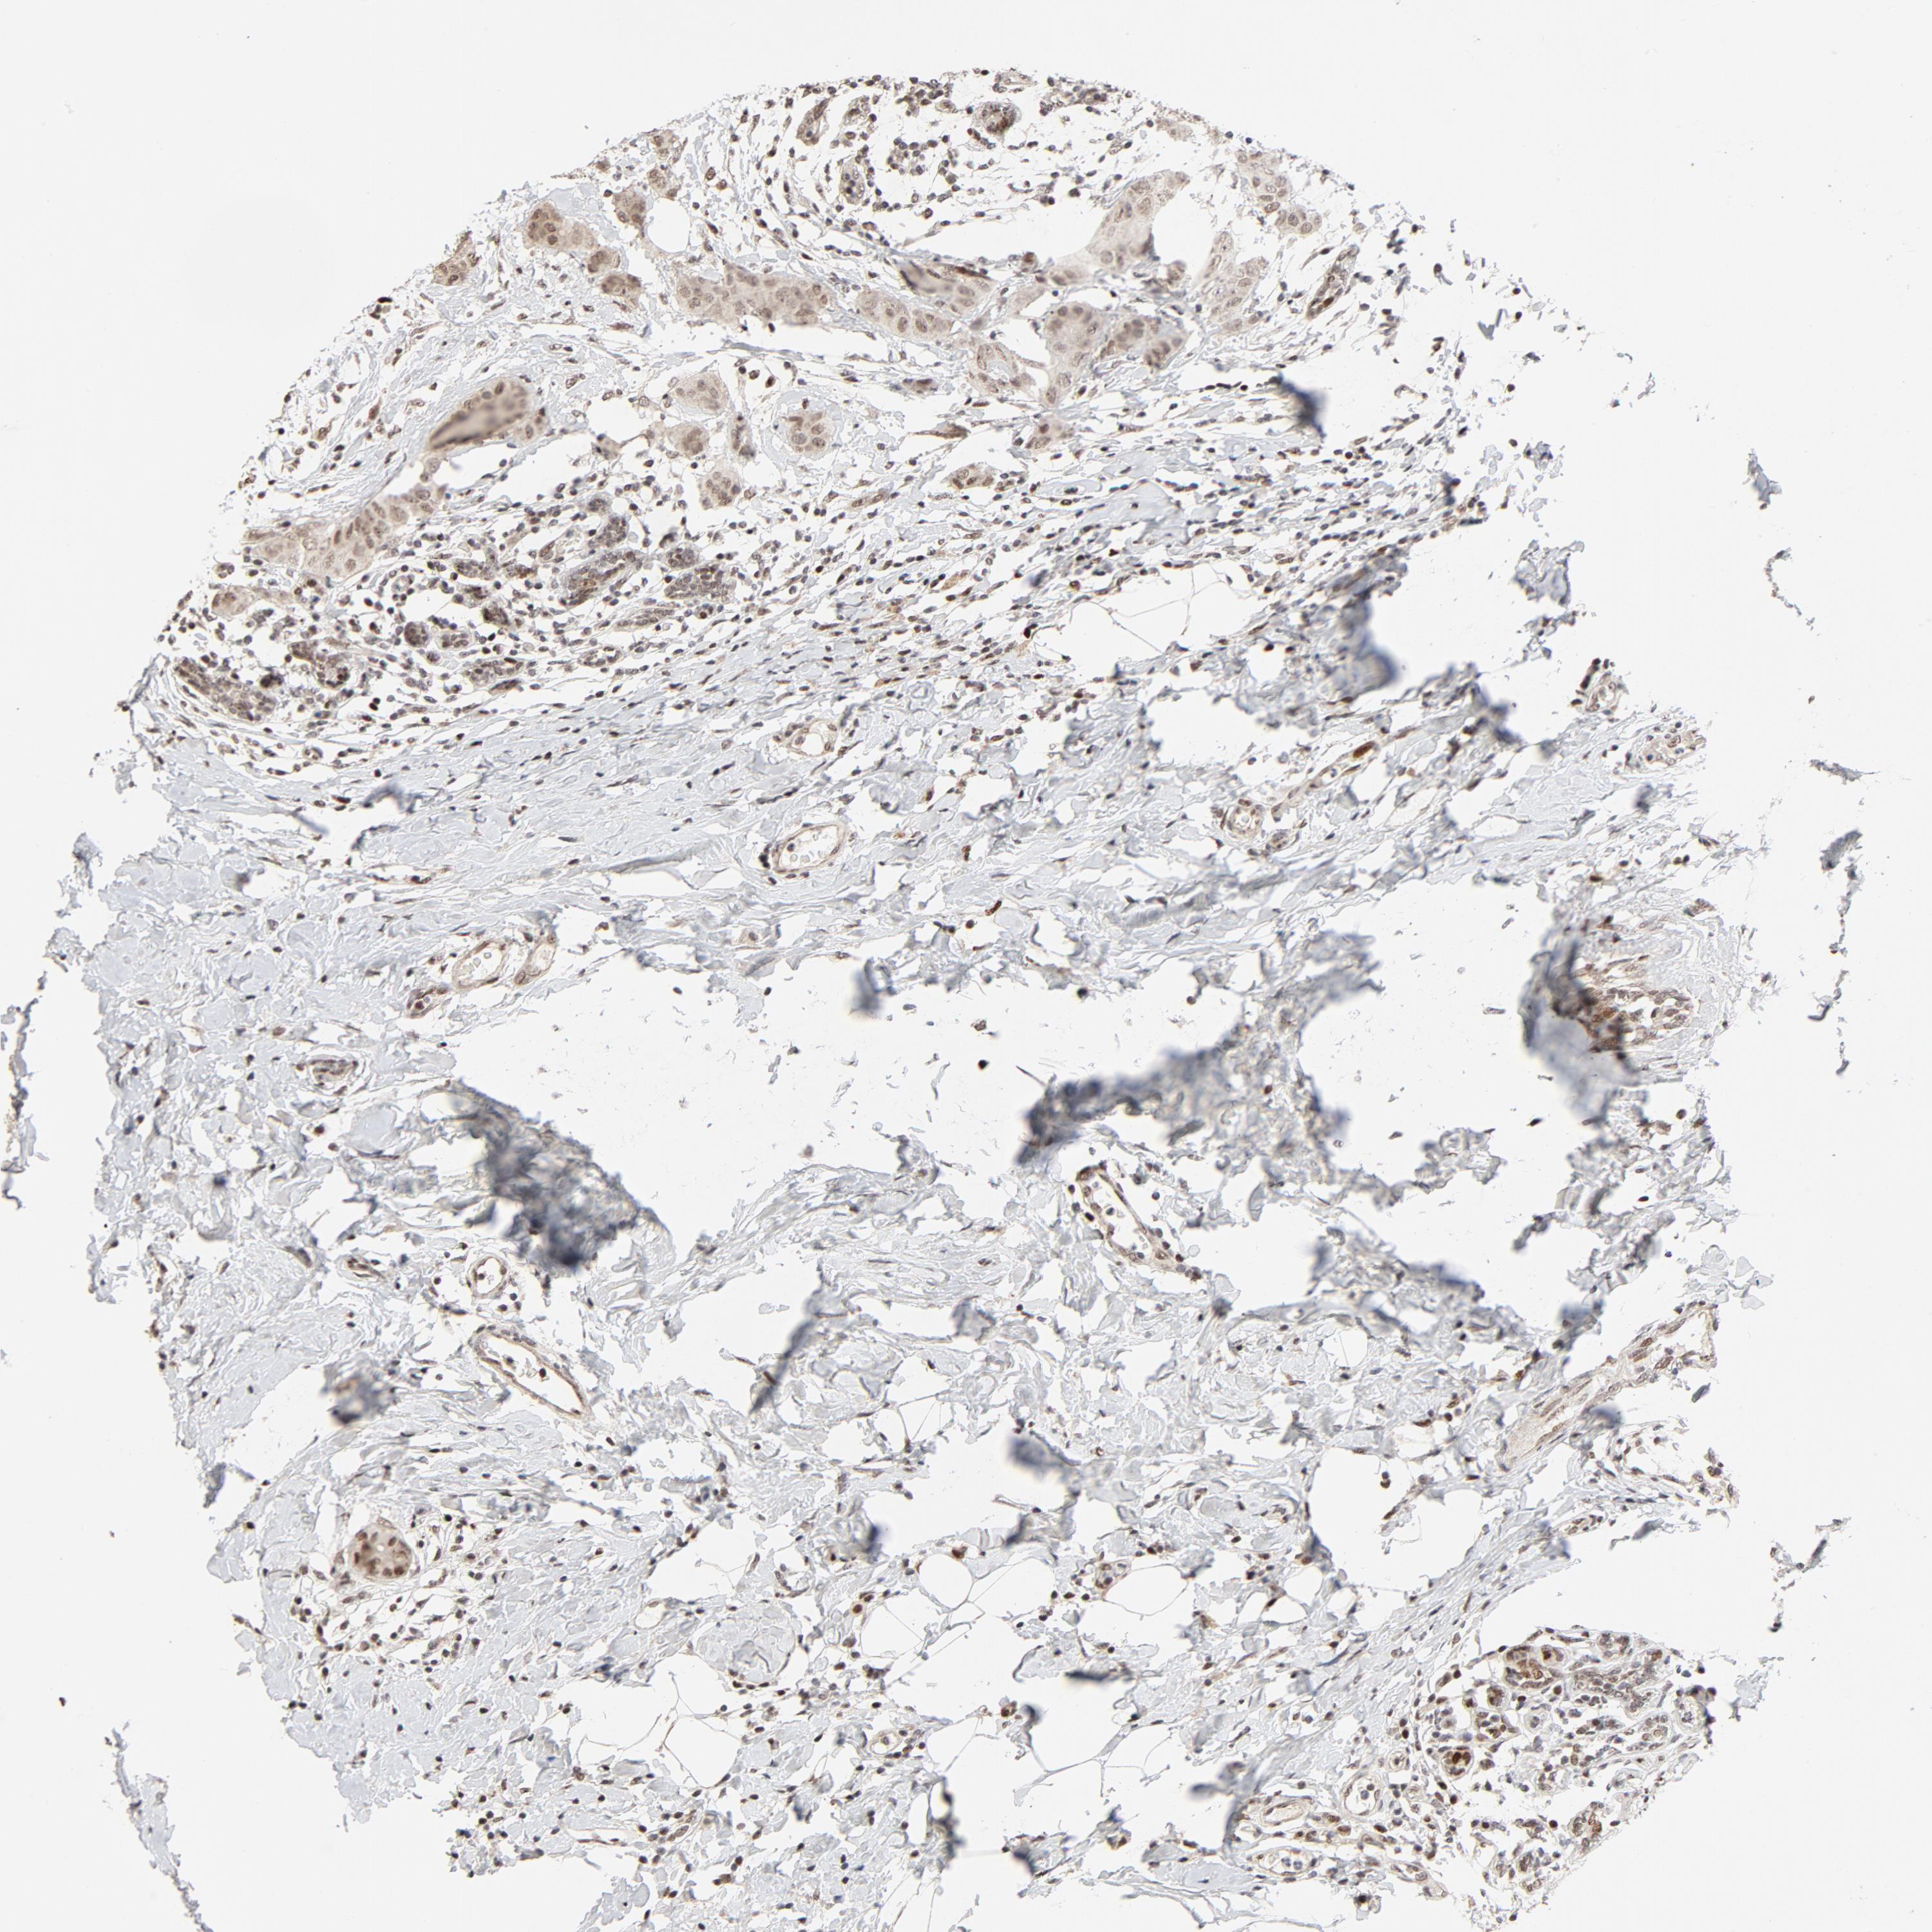

BRCA TCGA BRCA VALIDATION PROTEIN EXPRESSION

Breast cancer

Human cancer